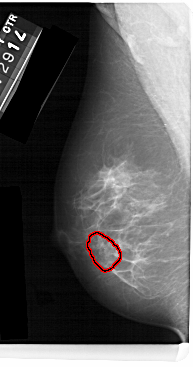

FILE: A_1477_1.LEFT_MLO.OVERLAY

TOTAL_ABNORMALITIES 1

ABNORMALITY 1

LESION_TYPE CALCIFICATION TYPE AMORPHOUS DISTRIBUTION CLUSTERED

ASSESSMENT 4

SUBTLETY 3

PATHOLOGY BENIGN

TOTAL_OUTLINES 1

LEFT_MLO LINES 5491 PIXELS_PER_LINE 2881 BITS_PER_PIXEL 12 RESOLUTION 43.5 OVERLAY